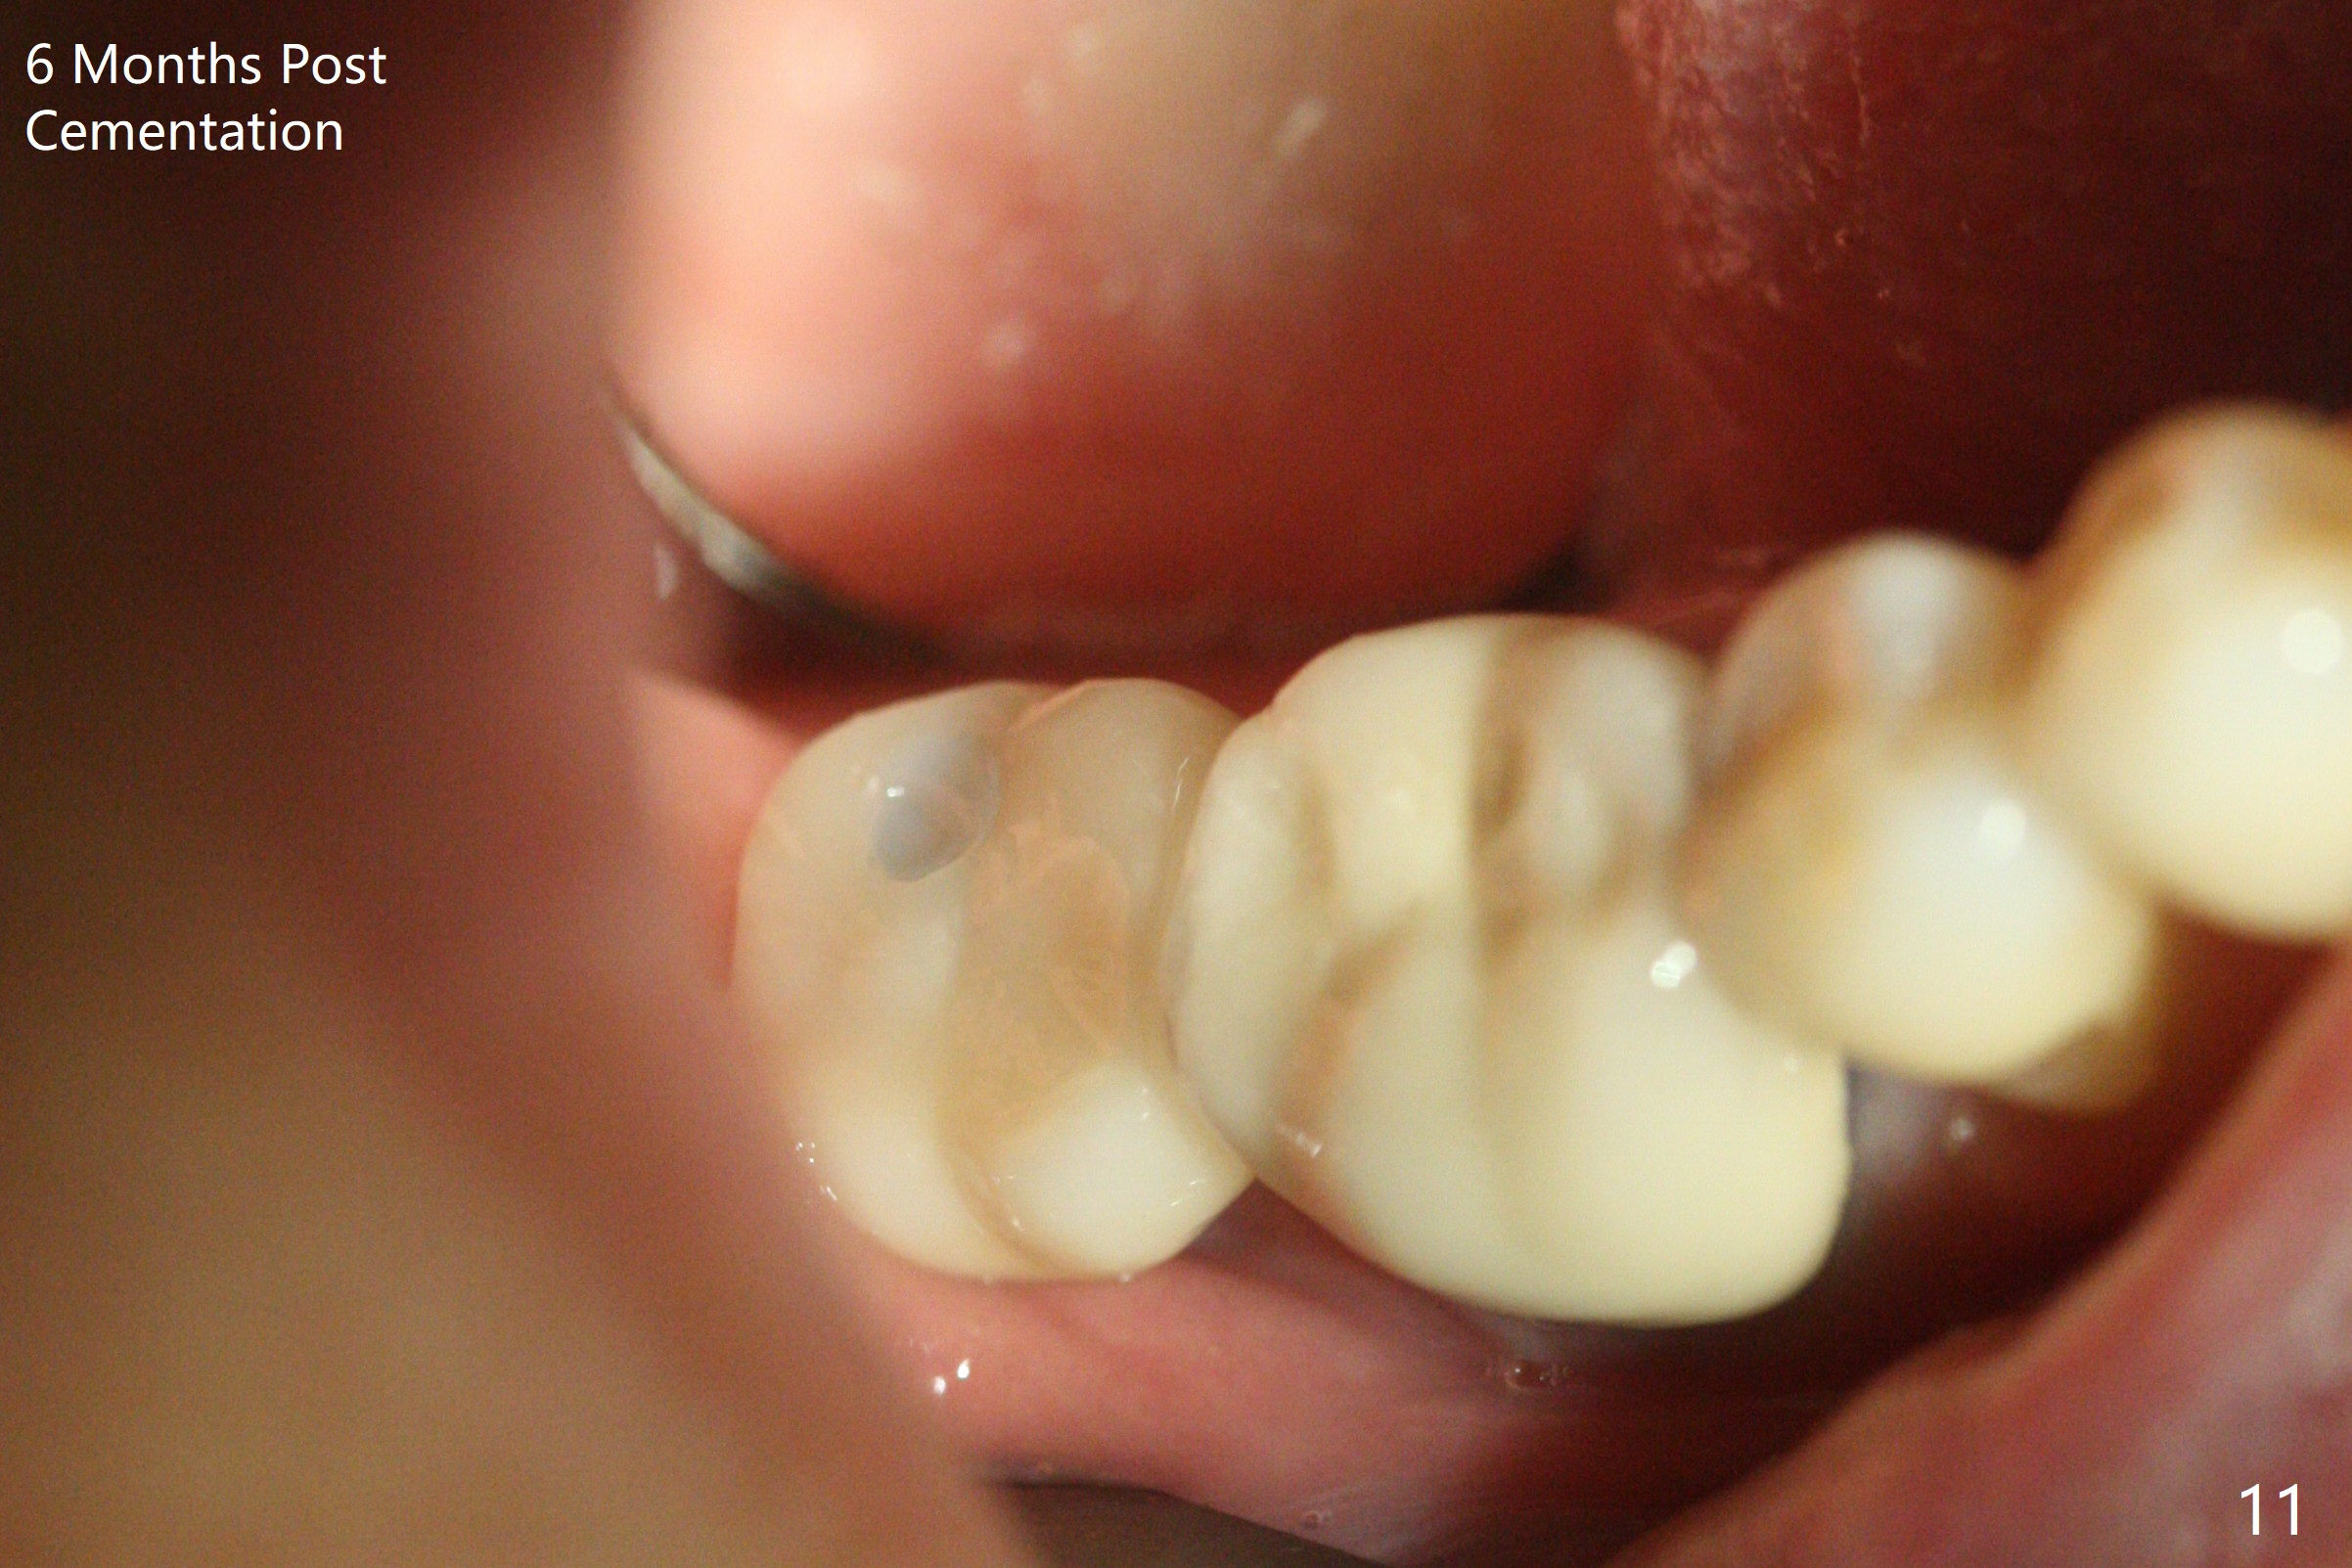

The trajectory is not right, since no matter how the sensors are placed, the implant threads cannot be shown clearly (Fig.10), in consistence with the distolingual access hole (Fig.11).